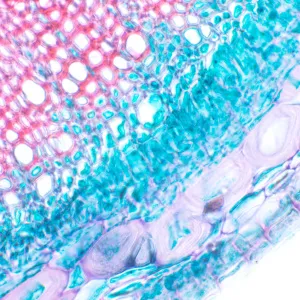

Микроскоп предназначен для наблюдения прозрачных и полупрозрачных биологических образцов в виде мазков и срезов в проходящем свете в светлом поле. Установка опциональных компонентов позволит использовать методы темного поля, фазового контраста и поляризации. Микроскоп подходит для рутинной лабораторной работы, научных исследований, обучения.